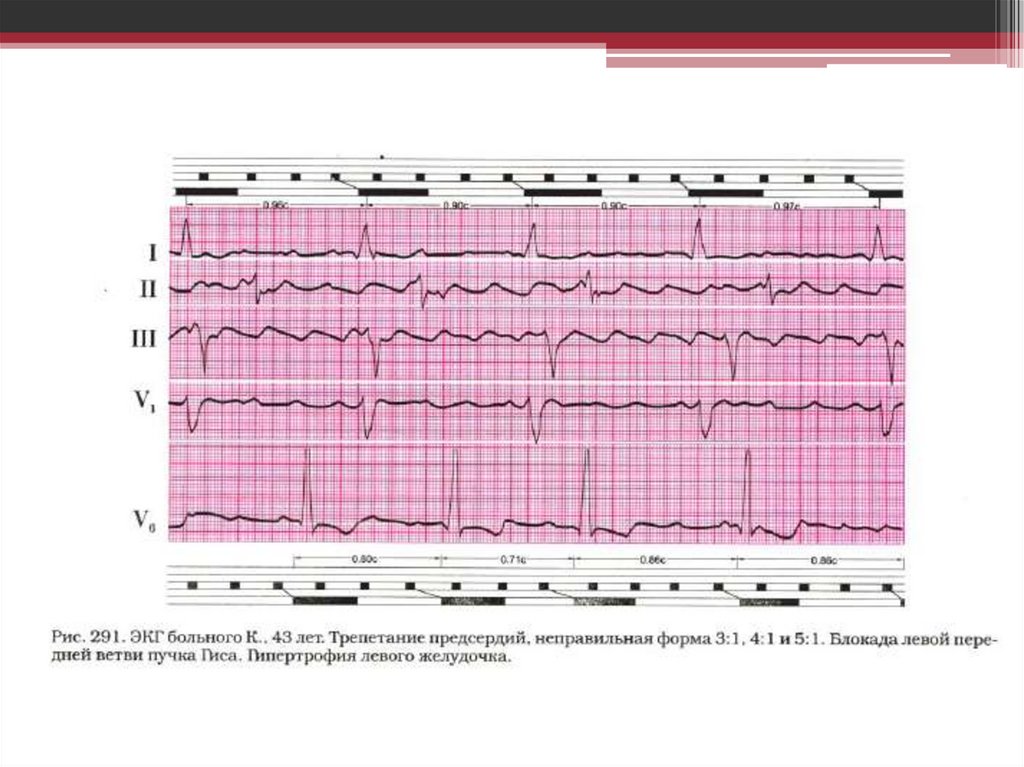

Атриовентрикулярная блокада - это нарушение проведения электрического импульса от предсердий к желудочкам.

28. Трепетание предсердий (ТП) – это значительное учащение сокращений предсердий (200-400) чаще при сохранении правильного

предсердного ритма.

Признаки на ЭКГ:

• частота сокращений

предсердий(зубцов Р) до 200-400в

минуту;

• отсутствие изолинии между

зубцами Р(пилообразный зубец

Р);

• сокращения

желудочков(комплексы

QRS)обычно учащены, но

ритмичны;

• кратность желудочковых

сокращений по отношению к

предсердным сокращениям может

составлять 1:2, 1:3, 1:4;

• зубцы Р па ЭКГ обозначают

буквой «F».